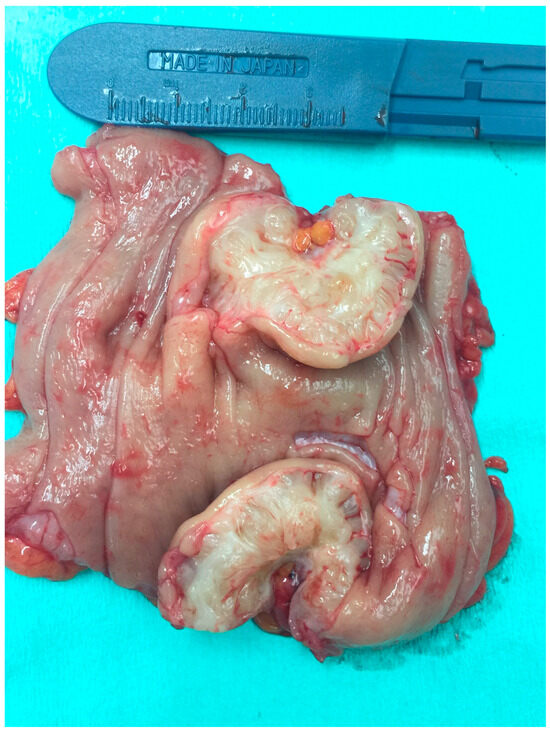

2.3. Acquisition and Measurements of Histopathological Samples